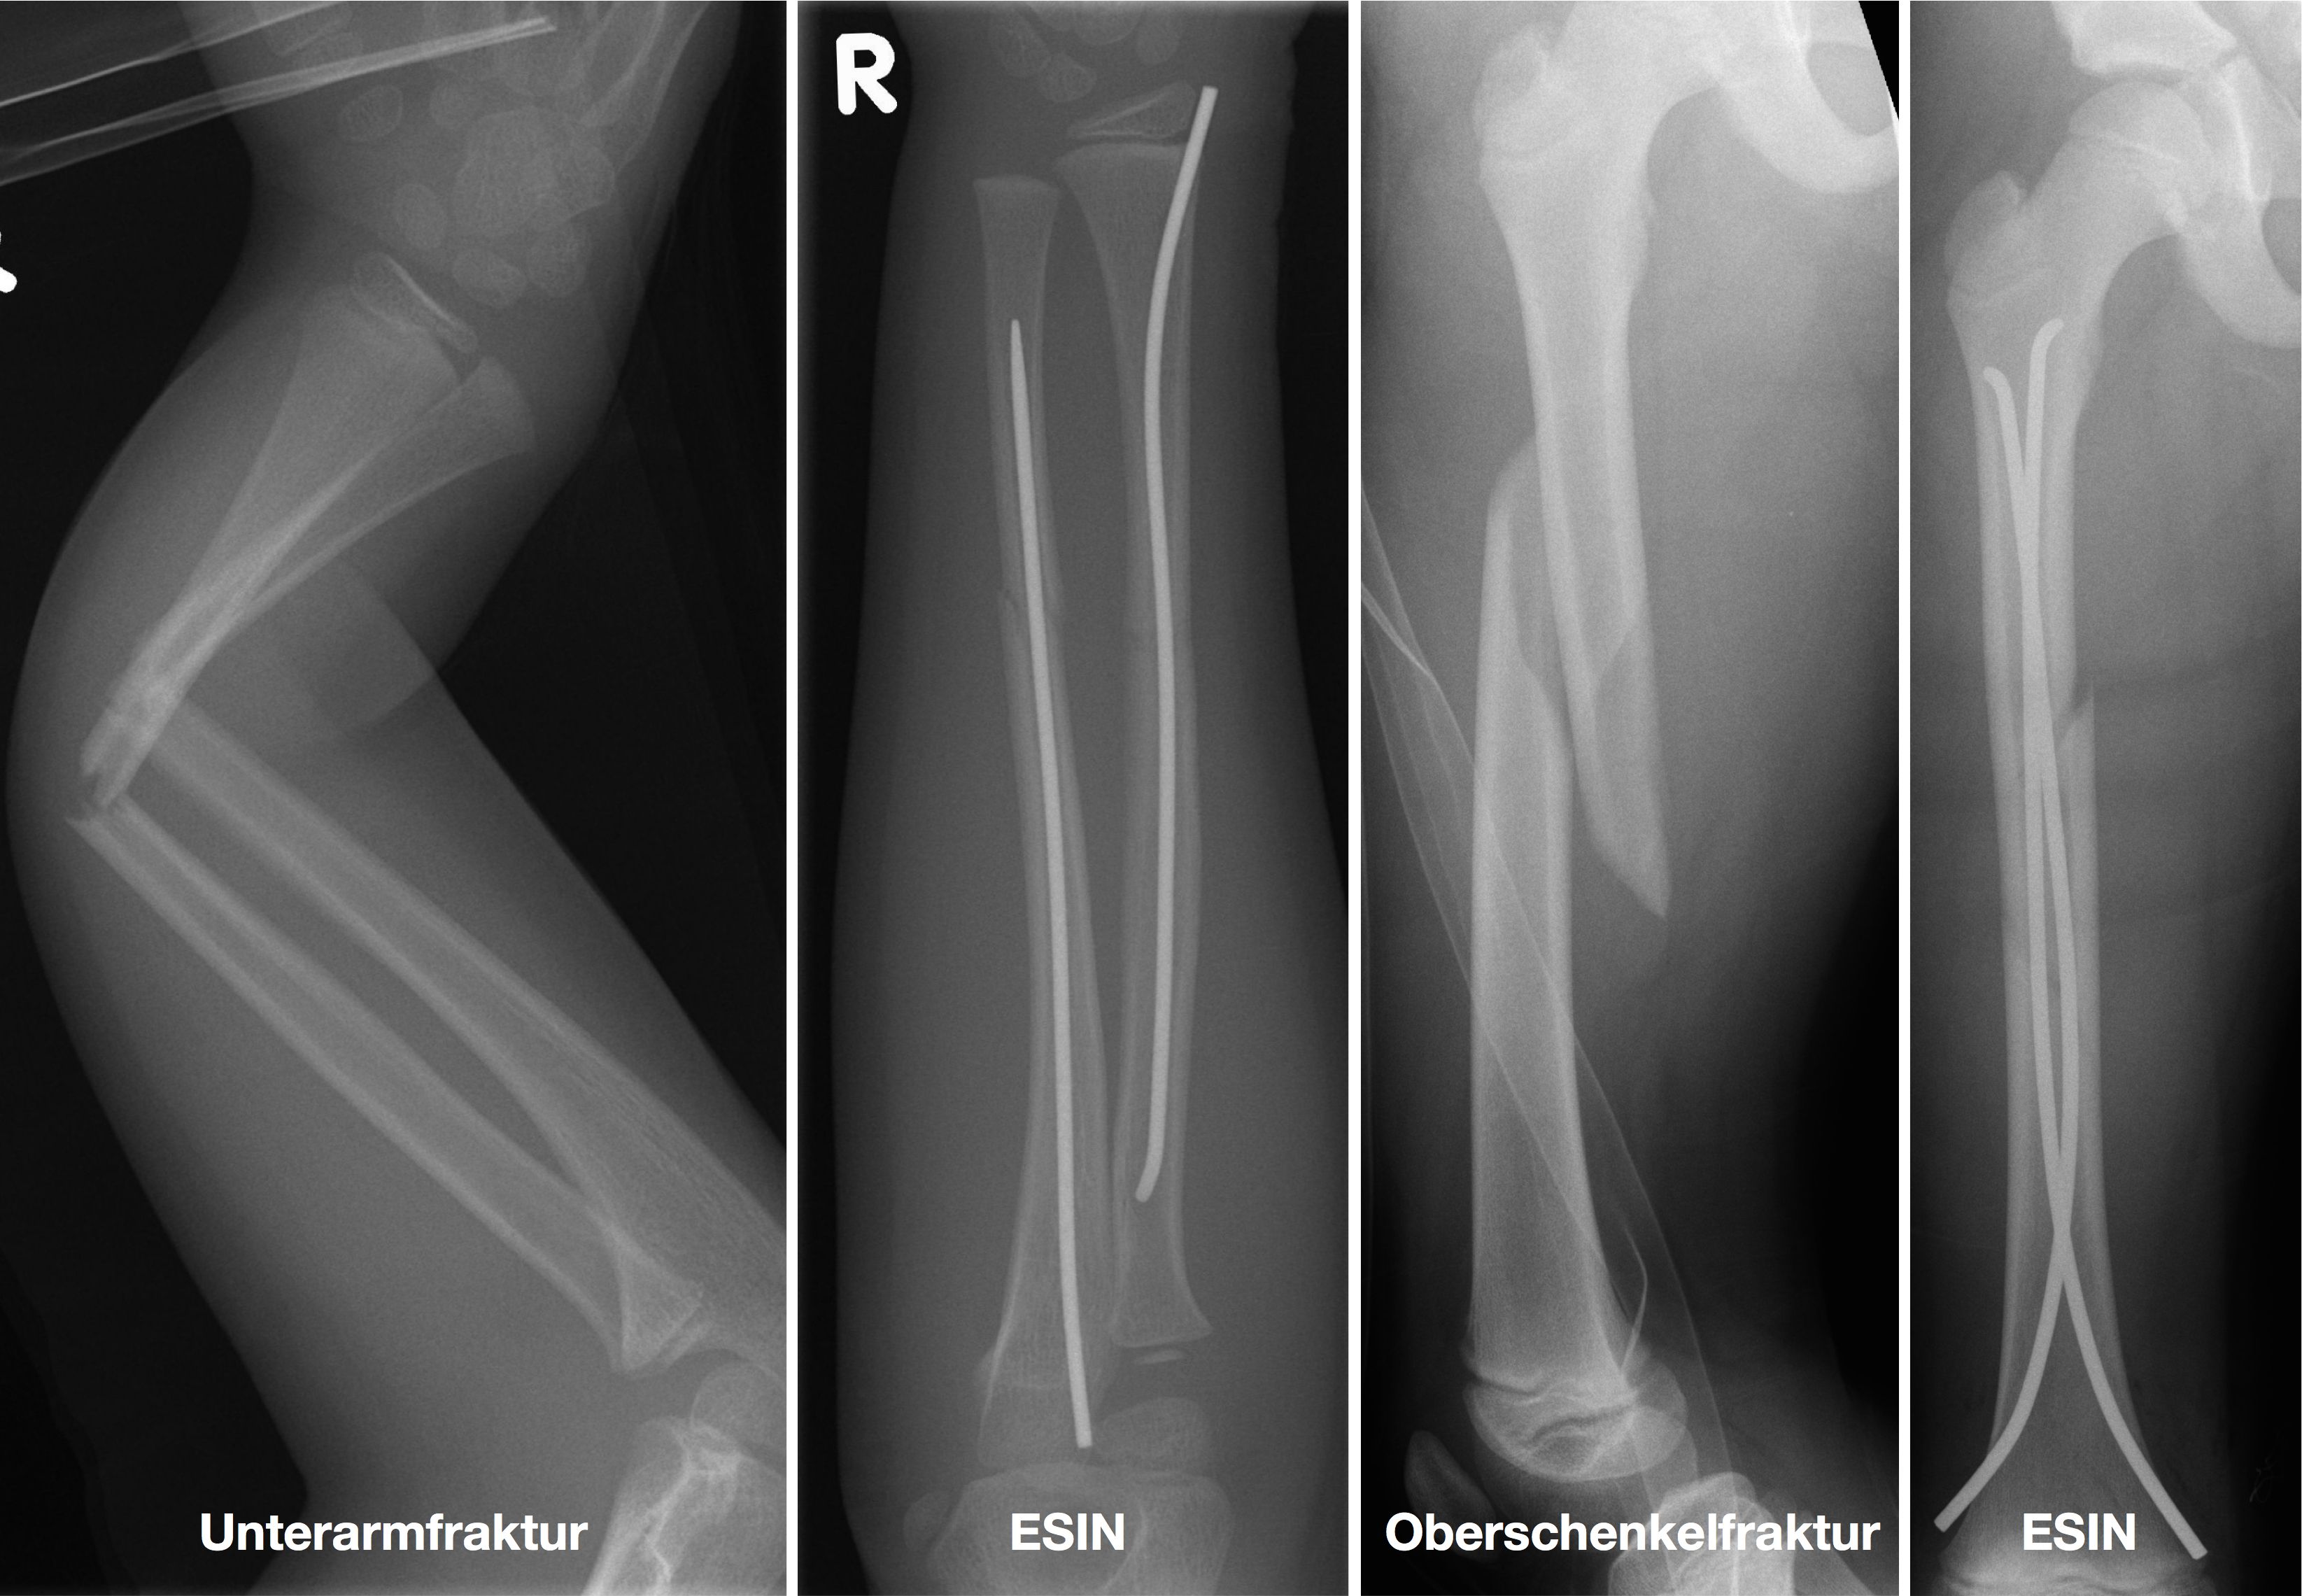

Einige Frakturen müssen auf Grund ihrer Achsabweichung operiert werden. In einer Narkose wird die Fraktur eingerichtet und ggf. mit Metall stabilisiert. Dazu stehen eine Reihe von Methoden (Osteosynthesen) zur Verfügung, die speziell für Kinder entwickelt wurden, um Wachstumsfugen zu schonen und nicht zu verletzen: Die ESIN (elastisch stabile intramedulläre Nagelung) hat sich als minimal invasives Standardverfahren zur Stabilisierung von Schaftfrakturen der großen Röhrenknochen (Unterarm, Oberarm, Unterschenkel, Oberschenkel) etabliert. Die Implantate können über winzige Schnitte eingebracht werden, eine gipsfreie Nachbehandlung ist ein weiterer entscheidender Vorteil.